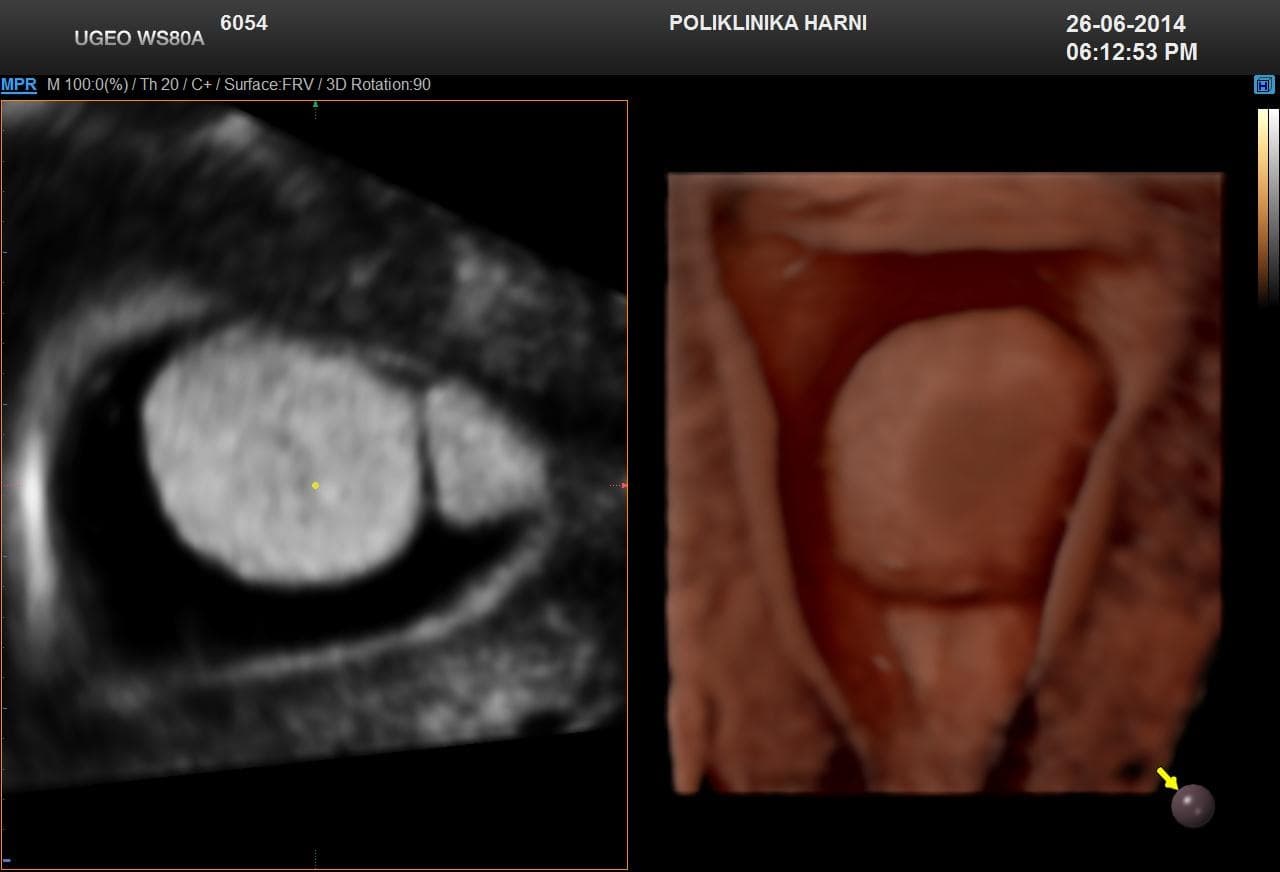

Kontrastni ultrazvukobojenim doplerom i 3D ultrazvukom / Hy-Co-Sy - hysterosalpingo-contrast-sonography sigurna je i učinkovita dijagnostička metoda u procjeni prohodnih jajovoda i od presudnog značenja u obradi neplodnih pacijentica. Provodi se u prvom dijelu menstruacijskog ciklusa nakon potpunog prestanka menstruacijskog krvarenja. Nakon pripreme pacijentice, u kanal vrata maternice se uvodi kateter i ubrizgava kontrast, a potom se prikazuju maternična šupljina, strukture unutar nje, eventualne anomalije maternice i prohodnost jajovoda. Kontraindikacije su trudnoća, krvarenje, akutna zdjelična upala i adneksalni tumor.

Pojava više-dimenzionalnog ultrazvuka omogućuje vizualizaciju ne samo određenih dijelova uterusa nedostupnih dvodimenzionalnom prikazu uslijed položaja uterusa, već i odabir optimalne ravnine kao i načina prikaza sumnjive lezije, a kod 5D ultrazvuka tehnološke inovacije omogućuju dodatne automatske presjeke koji omogućuju slojevitiju sliku i daju dubinu slici ujedno poboljšavajući dijagnostičku točnost. U dijagnostici anomalija uterusa trodimenzionalna rekonstrukcija ima prednost nad dvodimenzionalnim prikazom, te se njegova točnost može mjeriti s točnošću histerosalpingografije.

5D ultrazvučna tehnologija označuje dodatnu, vrhunsku kvalitetu revolucionarnog ultrazvučnog sustava uz automatizaciju tehnike koja više nije apsolutno ovisna o ultrasoničaru, uz najveću kvalitetu dijagnostičkog prikaza na LED monitoru i optimiziranim softverom, koji omogućuje novu slojevitu, dubinsku sliku poput CT prikaza u stvarnoj trećoj dimenziji u svim otvorenim pitanjima kako u ginekologiji, tako i opstetriciji.